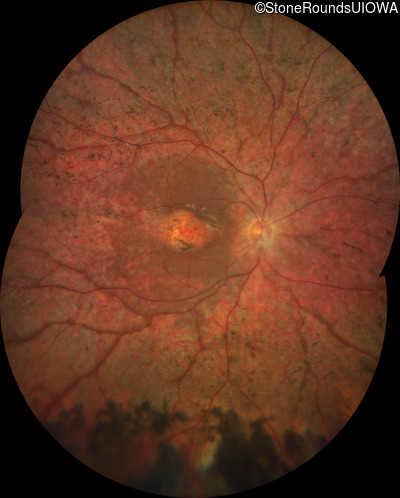

Fundus Photography - Right - 20/160

Exemplar

Fundus Photography - Left - 20/80 -1

Diagnosis & molecular findings

| Disease |

Gene |

Allele 1 variant(s) |

Allele 2 variant(s) |

Inheritance mode |

| ECORD |

CRB1 |

Gly770Ser GGC>AGC |

Cys896Stop TGT>TGA |

AR |